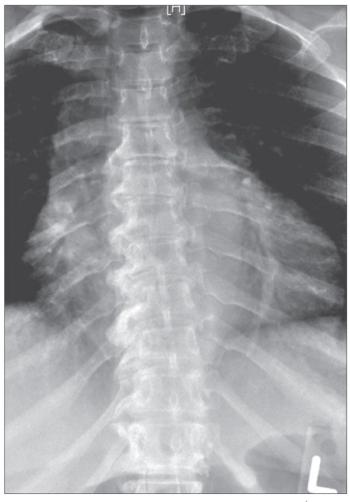

DISH, a radiographic finding characterized by abnormal calcification and ossification in the axial skeleton and in ligaments and entheses,1 most often affects the thoracic spine. Of note, the findings almost always are more prominent on the right side (the left side may be spared because of aortic pulsations). The enthesopathy, also called“whiskering,” can affect the pelvic brim, ischial tuberosities, greater trochanters, and other features that have ligamentous attachments.2 Diagnosis often is made after an incidental finding in an asymptomatic patient.